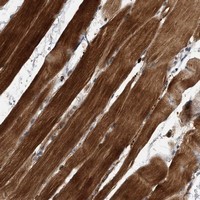

- Immunohistochemical staining of human skeletal muscle with SOBP polyclonal antibody (Cat # PAB22261) shows strong cytoplasmic positivity in myocytes at 1:200-1:500 dilution.

- Immunohistochemistry (Formalin/PFA-fixed paraffin-embedded sections)